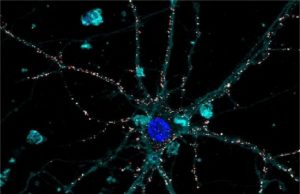

Nanotechnology applied to medicine: The first liquid retina prosthesis

Research at IIT-Istituto Italiano di Tecnologia (Italian Institute of Technology) has led to the revolutionary development of an artificial liquid retinal prosthesis to counteract...